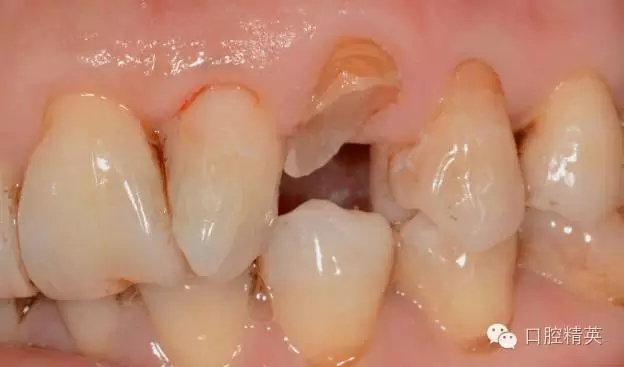

口內(nèi)檢查: 23殘根,位于齦上3MM,根管口探無反應(yīng),叩(+-),無松動,牙周無紅腫.X片示:23根管無阻射,根尖骨密度降低.

圖1 23口內(nèi)修復(fù)前情況:殘根位于齦上3MM,牙周無紅腫.